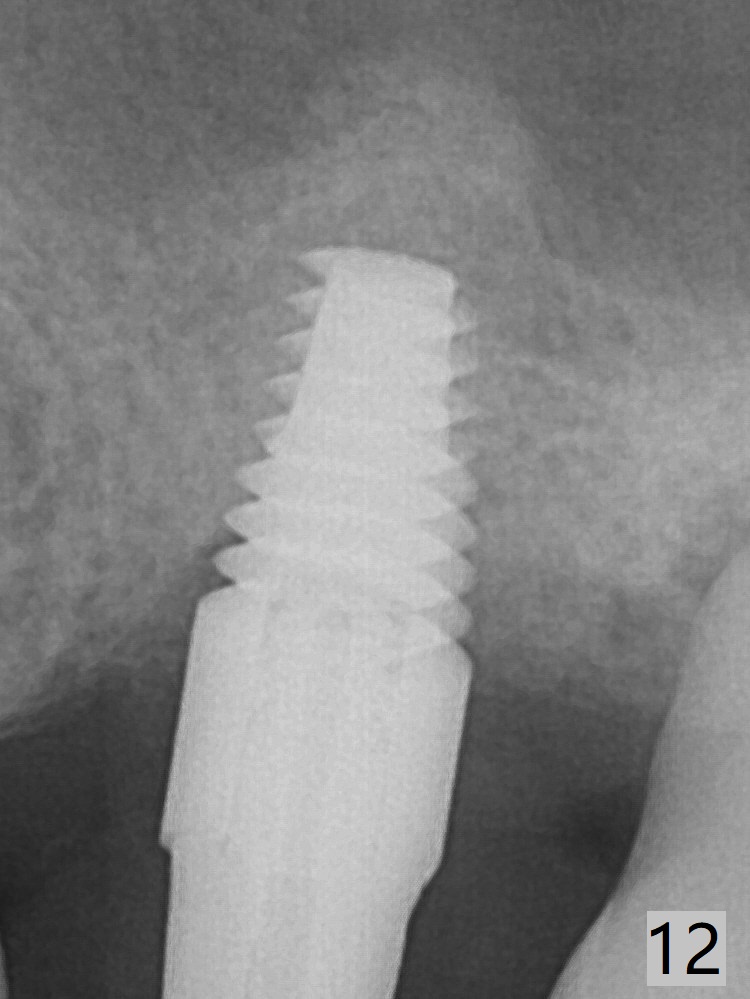

Depth of osteotomy is controlled with IS drill stoppers. After sequential osteotomy free hand, a 5x11 mm Tatum tapered tap is used to break through the sinus floor (Fig.5) and later sinus lift is conducted with the tap, a 5x11 mm implant and Vanilla allograft (Fig.6 *). When the implant is placed deeper (Fig.7 arrow), more bone condensation and sinus lift occur (arrowheads). Allograft is packed in the remaining socket gaps (Fig.9 *). The bone in sinus lift is mature 5 months postop (Fig.12,13). The first 1-2 implant threads are expected to be filled with mature bone in the near future (*). Since the abutment seems long enough for retention, temp bond is used for cementation (Fig.14). Water pik is being applied.